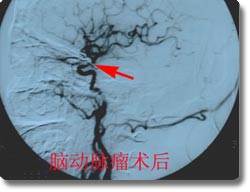

开展了脑动脉瘤、脑血管畸形、颈内动脉海绵窦瘘、脊髓血管畸形的神经介入治疗和恶性肿瘤的次选择性化疗,尤其是对巨大动脉瘤的栓塞成功率达到国内领先水平。同时开展了脑动脉瘤、动静脉畸形、高血压脑出血的手术治疗和血管闭塞性疾病的颅内外搭桥手术、颈内动脉内膜切除术、急性栓塞的溶栓治疗术、血管内支架放置手术,颅内动脉瘤电解可脱性螺旋圈(CDC)治疗,先后收治病人4000余例,积累了丰富的经验,为脑血管狭窄、脑供血不足及脑血栓病人的康复提供了有力保证。介入治疗具有不出血、无感染、损伤小、风险小、恢复快的优点,是脑血管疾病病人的理想选择。2003年,与北京宣武医院强强联合成立了北京市脑血管病中心重庆分中心。2005年成功地承办了第七届全国神经外科血管内治疗研讨会,受到了与会专家的一致赞誉。